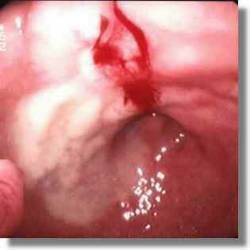

Un paciente ingresa con el diagnóstico de hemorragia digestiva alta en situación hemodinámica estable. Se practica una gastroscopia que informa: «Lesión ulcerada en cara posterior de bulbo duodenal con hemorragia activa no pulsátil. Forrest Ib. Se practica esclerosis endoscópica con adrenalina consiguiéndose hemostasia». Señala la afirmación correcta:

Answer

• La lesión descrita tiene un riesgo bajo de recidiva hemorrágica.

• En caso de recidiva hemorrágica es imprescindible la intervención quirúrgica.

• Por la localización de la lesión puede estar afectada la arteria gastroduodenal.

• La descripción y localización de la úlcera sugieren una lesión de Dieulafoy.

• En caso de intervención quirúrgica es obligatoria la práctica de una vagotomía troncular.